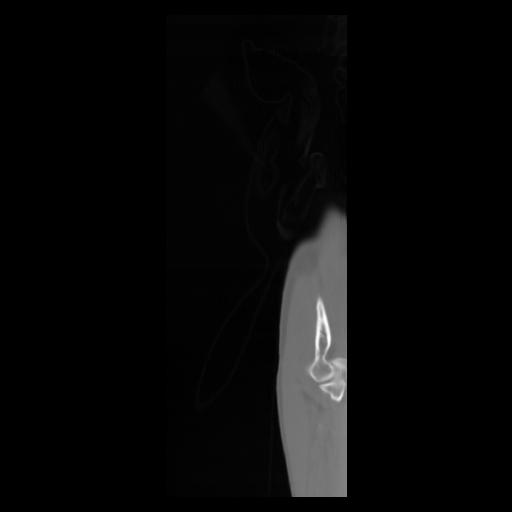

30 CUERPO,CE,Sagittal,3.000,CUERPO,Sagittal,